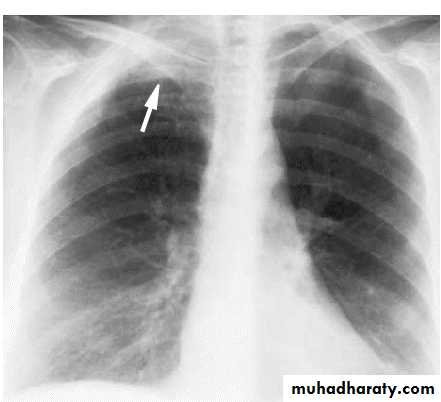

X-ray pneumothorax